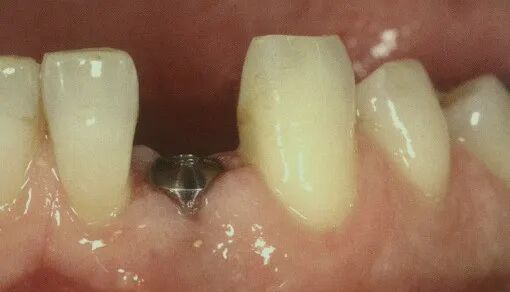

①圆柱形愈合基台 端部直径一致,呈柱状,且不同型号愈合基台穿龈高度一致,因此可根据穿龈深度选择合适高度的愈合基台。

②应用圆柱形愈合基台的种植系统中,二期手术时应充分去除妨碍愈合基台就位的骨组织阻力,以免造成愈合基台未完全就位的情况,影响最终修复体的戴入。

②愈合基台的端部用于牙龈袖口的成形,可选择端部高度合适的愈合基台,进一步成形牙龈。

②锥状的愈合基台诱导牙龈外型的位置是顶端及直径最大处,所以愈合基台选择时应选择最高端平齐牙龈或高于牙龈1mm;

③而柱状的愈合基台与复合型的愈合基台,牙龈成型的位置是在较低的位置,所以选择时柱状愈合基台最低平面平行牙龈即可;